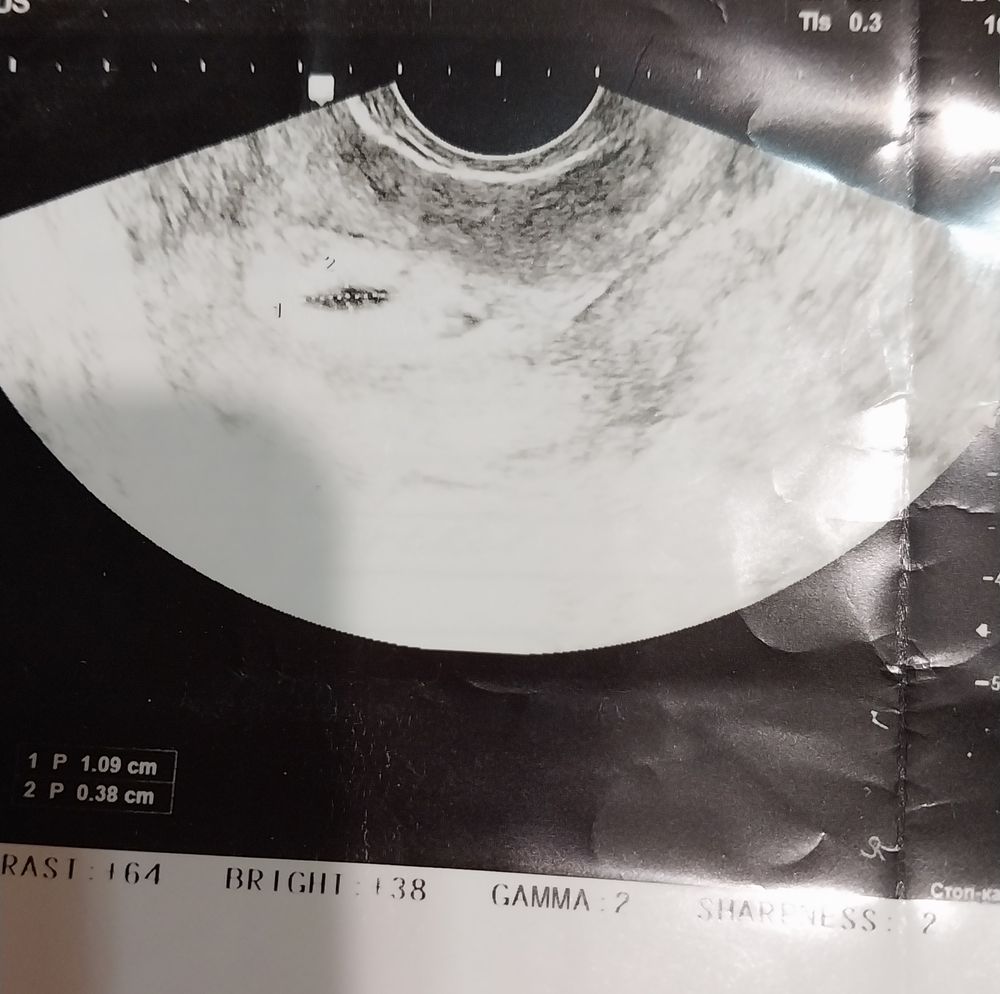

Следующее узи было у моего врача в клинике через неделю 7.03 и оно оказалось хуже предыдущих - деформацие пя, пя неправильной формы- элипс, зб под ? Пя напоминало летающую тарелку, и опять отставало по всем срокам. Хгч к тому времени я больше не сдавала не хотела себя расстраивать еще больше. Конечно у меня встал вопрос, а стоит ли ждать чего то дальше ?? Морально я все таки не была готова к прерыванию пусть и с таким херовыми показателями…Мой врач сказала что решать только мне, все конечно очень плохо и низкий хгч и форма плодного яйца и отсутствие жт, но решение все таки за мной…и я решила ждать еще !

Вот мой эмбрион, а говорили анэмбрионию. Я понимаю что замер, но диагноз неверный сказали, а при хорошем аппарате увидели.